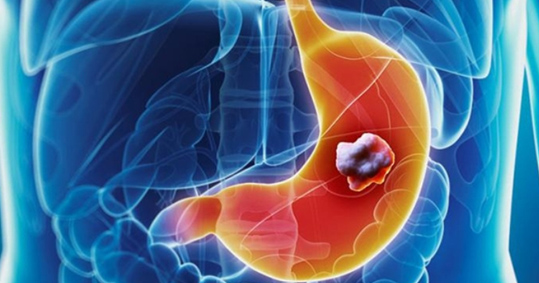

Πεπτικό έλκος είναι η διάβρωση του επιθηλίου του βλεννογόνου του στομάχου ή του δωδεκαδακτύλου, η οποία μπορεί να επεκταθεί μέχρι και τη μυϊκή στοιβάδα. Η διάβρωση αυτή προκύπτει από την ανισορροπία μεταξύ των ‹‹αμυντικών ή προστατευτικών μηχανισμών›› του πεπτικού (βλέννα, επιθηλιακά κύτταρα του βλεννογόνου, διττανθρακικά, επαρκής αιματική ροή) έναντι των ‹‹επιθετικών μηχανισμών›› του πεπτικού.

Το πεπτικό έλκος διακρίνεται σε δύο κατηγορίες: Έλκος στομάχου και έλκος δωδεκαδακτύλου.